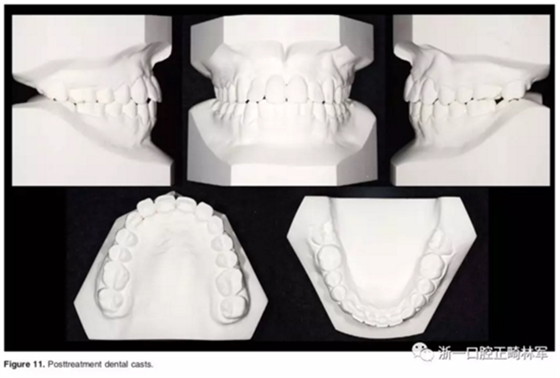

口外相:前牙易位、阻生均得以正確糾正,牙周組織健康。

口內(nèi)相及模型:I類尖牙、磨牙關(guān)系,覆合、覆蓋正常;中切牙與側(cè)切牙間有輕微的轉(zhuǎn)矩差;牙齦外形可;此外,在治療期間病人的口腔衛(wèi)生不夠良好,導(dǎo)致幾顆牙齒出現(xiàn)了齲病。

2年隨訪:咬合關(guān)系保持穩(wěn)定,無明顯復(fù)發(fā),下頜有一定晚期生長趨勢;前牙牙齦外形、牙冠高度無明顯變化;唇側(cè)牙槽骨高度、厚度均保持良好。